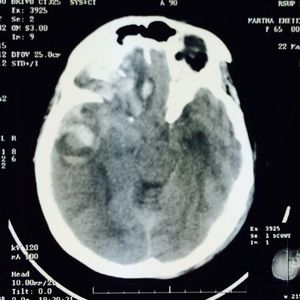

Brain contusion